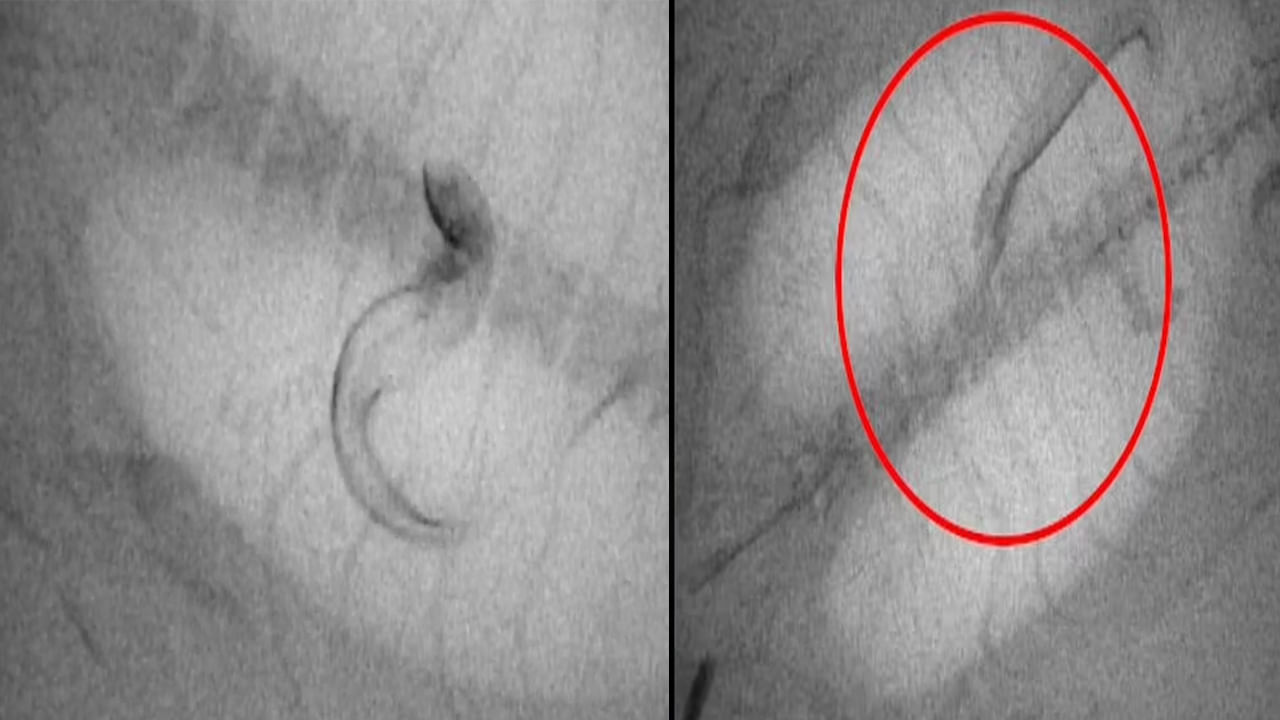

కొన్ని జంతువులకు పదునైన ముళ్లు లేదా తమను తాము రక్షించుకునేందుకు తమ శరీరంలోనే కొన్ని నిష్క్రియాత్మక రక్షణలు ఉంటాయని పరిశోధకులకు అంటున్నారు. అవే వాటికి వేటాడిన జంతువుల నుంచి బయటపడేందుకు సాయపడతాయట. పరిశోధకులు సుమారు 32 జువెనైల్ ఈల్స్కు ఎక్స్-రే వీడియో సిస్టమ్కు కనిపించేలా చేసే కాంట్రాస్ట్ ఏజెంట్ను ఇంజెక్ట్ చేశారు. తర్వాత వాటిని చిన్న ట్యాంకులలోని డార్క్ స్లీపర్( ఓడోంటోబుటిస్ అబ్స్క్యూరా) అనే పిలిచే చేపలోకి పంపారు.

ఆ చేప ఈల్స్ను తిన్న వెంటనే.. సదరు ఈల్స్ చేప కడుపు నుంచి తప్పించుకోవడానికి తీవ్రంగా ప్రయత్నించాయి. చివరికి కేవలం తొమ్మిది మాత్రమే ప్రాణాలతో బయటపడ్డాయని పరిశోధకులు పేర్కొన్నారు. కొన్ని కడుపులో తిరుగుతూ, బయటపడే మార్గాన్ని వెతకగా.. మరికొన్ని విజయవంతంగా తప్పించుకున్నాయని తెలిపారు.